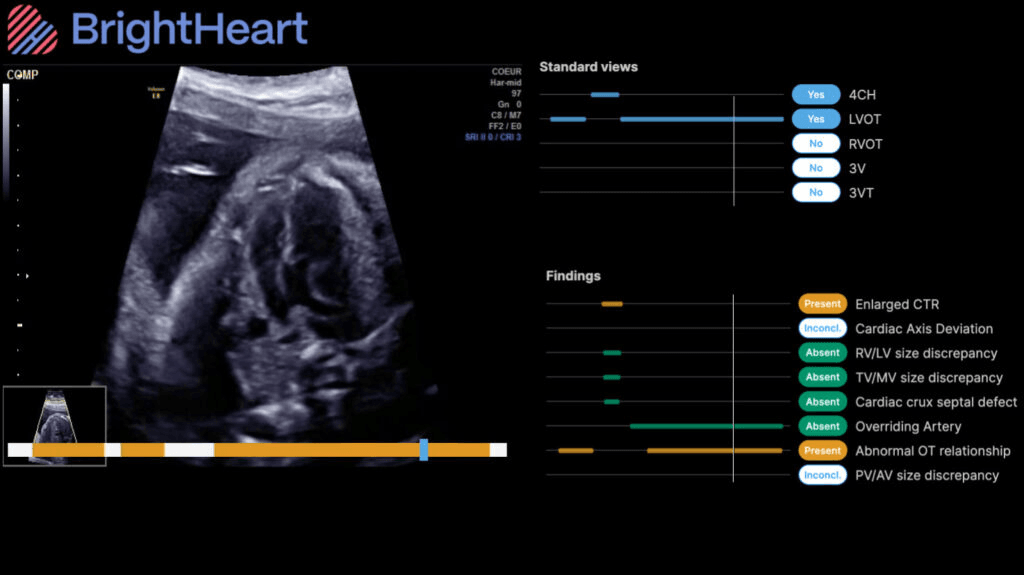

BrightHeart, a global leader in AI-driven prenatal ultrasound, recently announced the availability of its B-Right AI Platform through GE HealthCare’s Voluson Solution Store, bringing advanced AI support directly into routine prenatal care. The addition of this AI platform to the Voluson Solution store is poised to improve early detection of congenital defects, reduce diagnostic uncertainty, and ultimately support better outcomes for clinicians, expectant parents and their babies.

This collaboration combines BrightHeart’s innovative AI technology with GE HealthCare’s trusted Voluson ecosystem through the Voluson Solution Store – the first digital marketplace for Women’s Health ultrasound, available in the U.S. and Europe. Together, the companies are helping to democratize access to expertlevel prenatal care by making clinically validated AI for congenital defect screening and full scan support available to Voluson ultrasound users. Supported by strong clinical evidence – including two recent publications in The Green Journal – and developed with leading fetal cardiology and maternal and fetal medicine (MFM) experts, BrightHeart goes far beyond basic quality checks, delivering reliable, evidencebacked insights that reduce diagnostic errors and improve the detection of congenital defects while strengthening workflow efficiency. BrightHeart’s AI Platform enhances Voluson’s offering with a simple, intuitive, cloud-based solution that supports enhanced care spanning acquisition, interpretation, and review across care settings and workflows.